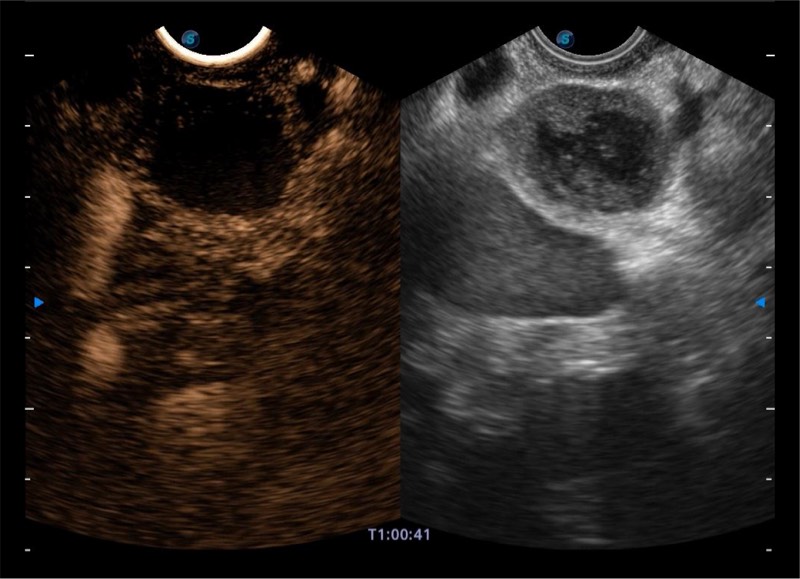

基于二十年的超声技术积累,milan米兰提供了最新一代的独立超声主机,在提供高质量图像的同时满足多学科使用。具备常见多普勒技术并提供弹性成像、声学造影等高端影像技术。新一代传感器具有更强的抗干扰能力并减少图像伪影。

4-12MHZ宽频输出